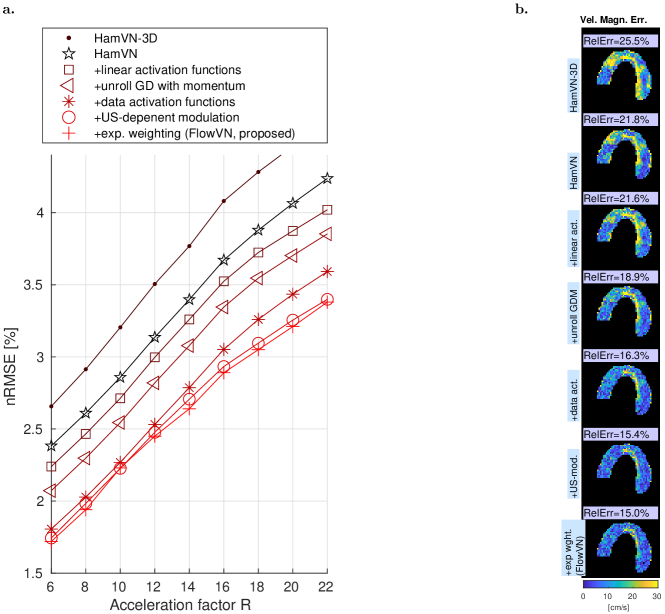

Reconstructed image magnitudes (for a single velocity encoding component), estimated velocity magnitudes and their errors of a healthy volunteer data for acceleration factor =14 are illustrated in Fig. 3 for retrospectively undersampled data. Compared to CS-LLR and HamVN, the proposed FlowVN provides better reconstruction accuracy in terms of image magnitude and velocities. Scatter plot and correlation analysis further suggest that the velocity magnitude image estimated via FlowVN is in better agreement with ground truth. As shown in Supplementary Table 2 these observations extend to other acceleration factors (6–22) as tested on 7 healthy volunteers.

In this work we have further developed the VN architecture 15, 36, 37 to accommodate high performance undersampled 4D flow reconstruction with limited training. Namely, we avoid exponential model complexity growth by avoiding 4D convolutions and by using separable 3D convolutions that are shared for real and imaginary parts of the image. Furthermore, in contrast to the original HamVN 15, we train our FlowVN for a wide range of undersampling factors by allowing the regularization term to depend on them. As illustrated in Fig. 2e, regularization scaled by decreases as more samples are available, while the data term stays constant for most of the layers. Such conditioning allows network training on a larger variety of artefacts and as it is necessary in practice, since for a given fixed acquisition time, the precise value of the undersampling factor is not known a priori and depends on breathing and cardiac motion patterns. We hypothesize that the wide range of acceleration factors which were used simultaneously to train the FlowVN provided a diverse collection of aliasing artefacts and enabled robust learning on a remarkably limited training set of 11 subjects. The exponential weighting of the layer-wise reconstruction loss (3) further regularized FlowVN parameters by penalizing the nonlinear behaviour presented in HamVN reconstructions. Supplemental Fig. 6 and Table 3 provide quantification of reconstruction accuracy effects attributed to the modifications proposed with FlowVN. In particular, modifications to the network architecture result in a model that can better adapt to data and yield higher accuracy for retrospectively undersampled experiments, while the proposed exponential weighting of the training loss improves accuracy of the prospective evaluation, which indicates better generalization ability. It is worth noting, that FlowVN has only 1% more tunable parameters compared to HamVN (c.f. Table 1), while improving reconstruction nRMSE by 23% (averaged over acceleration factors as given in Supplemental Fig. 6). We note that 4D flow MRI greatly benefits from using coil information during reconstruction (see Supplementary Table 3). Accordingly, comparison with single-coil reconstruction networks 18 has limited benefit.

The proposed FlowVN is a learning-based approach for reconstructing undersampled 4D flow MRI data in under a minute. For fixed reconstruction accuracy, FlowVN enables higher acceleration factors (12% improvement compared to CS-LLR image nRMSE at =16) and does not introduce significant bias of peak flow estimates. The proposed reconstruction is 30 times faster than state-of-the art CS-LLR and 4.2 times faster than HamVN, due to using linear activation functions rather than RBFs, which requires computation of pairwise distances between control knots and image intensities. It is worth noting that FlowVN demonstrates high generalization ability, being able to preserve patient pathologies that were not present in the training data.